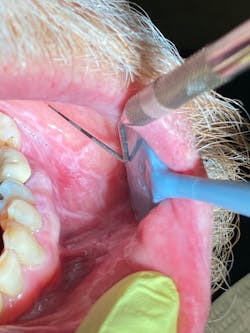

As I suspected, the initial diagnosis for this patient was lichen planus (LP) with ulcerative tendencies, even though there were no real prominent ulcers presenting at the time. The burning in the mouth that the patient was experiencing was more or less what initiated suspicion of the diagnosis.

Here’s a quick refresher on lichen planus. LP is an inflammatory condition that affects the mucus membranes of the mouth. Symptoms of burning, itching, pain, and overall discomfort can range from mild to severe. LP is a T-cell autoimmune disease commonly found in the fourth decade of life, and it affects men more than women.1 The buccal mucosa, tongue, and gingiva are the most common oral areas affected.1